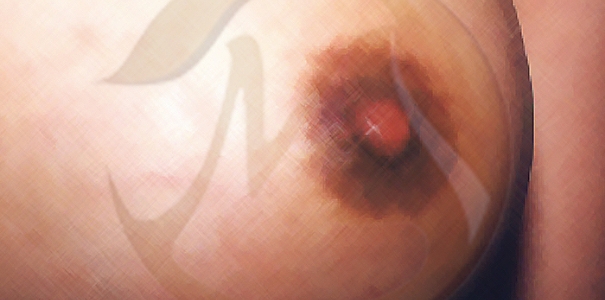

1단계

함몰된 유두가 손으로 쉽게 당겨지며 돌출이 유지됨 -